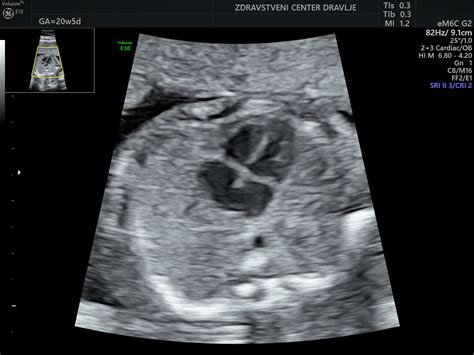

Na ultrazvoku v 23. tednu nosečnosti bi lahko opazili, da se otročku oblikujejo majhne bradavice. Obrazek ima že skoraj popolnoma izoblikovan - potrebuje le še malo maščobe, da se izpopolni. V tem tednu so nohti vašega otroka že skoraj popolnoma izgotovljeni, lanugo dlačice po telesu začnejo temneti.

Usmerjanje pozornosti na razvoj ploda lahko poteka preko različnih meritev, ki jih opravlja ginekolog. Pri tem se ocenjujejo posamezni deli plodovega telesa, kot so prečni presek in obseg glavice, obseg trebuha, dolžina stegnenice, ter razvoj kosti goleni. Te meritve se primerjajo s krivuljami rasti za posamezno kost. UZ-oceno glavice naredimo v treh ravninah - transtalamični, transventrikularni in transcerebelarni. V teh ravninah se ocenjujejo možganske strukture, velikost prekatov, ter razvoj malih možganov. Poleg tega se ocenjujejo tudi očnici, razdalja med njima, ter profil obraza, vključno z nosom, ustnicami in bradico. Hrbtenica se prikaže v različnih ravninah, ocenjuje se tudi trebušna prepona, ki razmejuje prsno in trebušno votlino. Prečni prerez čez prsni koš omogoča oceno velikosti, položaja in strukture srca, vključno s štirimi votlinami in izstopišči velikih žil. Prečni presek čez trebuh v nivoju ledvic omogoča pregled ledvic in želodca. Ocenjuje se tudi mehur in spolovilo. Pregled zgornjih udov vključuje prikaz nadlakti, podlakti in dlani. Viden je tudi vstop popkovnice v trebušno votlino, ter posteljica z barvnim Dopplerjem. Debelina posteljice je v tem obdobju v milimetrih enaka tednom gestacije. Popkovnica v prečnem prerezu prikazuje dve arteriji in eno veno, obdani z Whartonovo želatino. Dolžina materničnega vratu se meri od notranjega do zunanjega materničnega ustja, ocenjuje se razprtost NMU in oddaljenost do posteljice. Na 3D-slikah lahko opazimo obliko in položaj ušes, ter lep obrazek z vse več podkožnega maščevja, rdečkasto kožo, lanugom, ustnicami, nosnicami in vekami. Ker plod v maternici vedno bolj raste, se lahko količina plodovnice zdi manjša, vendar je normalno, da je plodovnice več, kot zaseda volumen ploda.